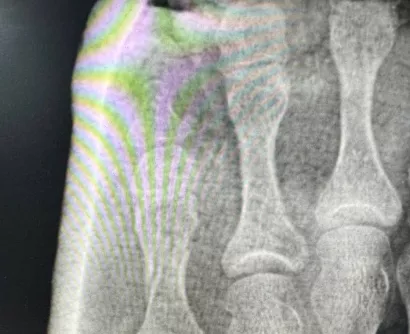

Осмотр и рентгенография позволили поставить диагноз — оскольчатый перелом проксимальной фаланги 5-го пальца. Иван Александрович выполнил репозицию (сопоставление) отломков кости и иммобилизацию стопы гипсовой лангетой. Контрольная рентгенограмма после процедуры позволила оценить результат и убедиться в восстановлении фрагментов. Пациентка довольная уехала домой.

Перелом пятого пальца левой стопы (1) и после репозиции кости и иммобилизации гипсовой лангетой